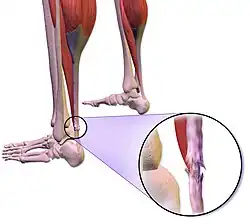

Rupture du tendon d'Achille

Le tendon est relativement fragile et les accidents (ruptures) sont fréquents, principalement au cours d'activités sportives (tennis, volley-ball, badminton…), ou lors de traitements par antibiotique de type fluoroquinolone.